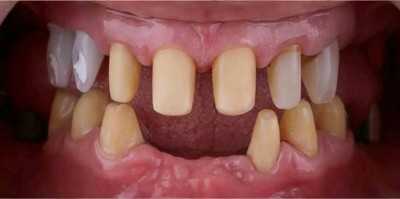

Озеров Петр специализируется на хирургической стоматологии и импланталогии, блестящий специалист по лечению и удалению кисты. Является постоянным участником курсов, семинаров и международных конгрессов по имплантологии и ортопедии. Петр Владимирович проводит протезирование как классическими методиками керамикой и металлокерамикой, так и протезами на драгсплавах (диоксид циркония, алюминий), и эстетическое протезирование винирами и люминирами. Кроме протезирования и имплантации, доктор выполняет и хирургическую подготовку к ним: операции по костной пластике с применением искусственной кости и аутокости (собственной кости пациента).